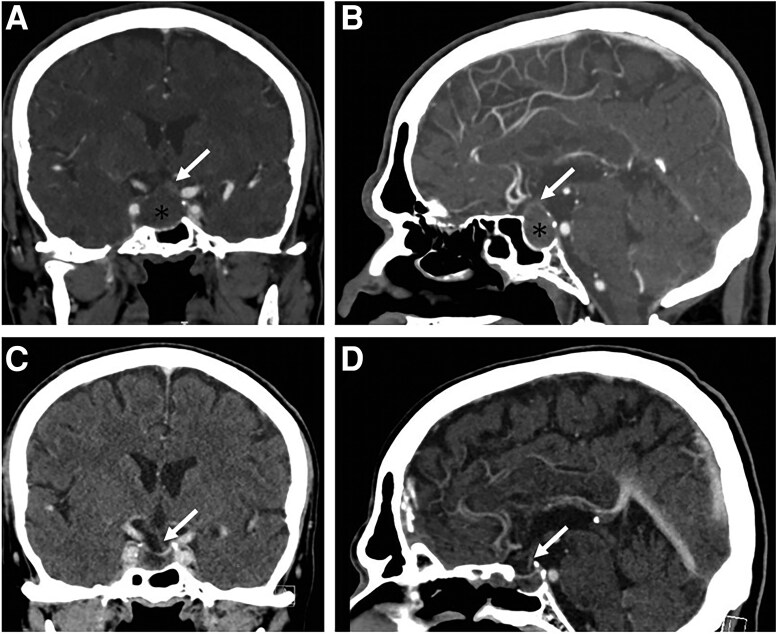

Thyroid-stimulating hormone (TSH; thyrotropin) adenoma is a rare pituitary tumor that can be missed due to its subtle symptoms. We are reporting a 67-year-old man with history of ventricular fibrillation on amiodarone who presented with acute headache and right third cranial nerve palsy. His computed tomography (CT) scan revealed a 2.2-cm suprasellar mass, consistent with pituitary apoplexy, and he underwent pituitary tumor resection. Preoperational hormonal workup revealed TSH 0.25 mIU/mL (0.25 IU/L) (normal reference range: 0.35-4.94 mIU/mL; 0.35-4.94 IU/L), free thyroxine (T4) 3.17 ng/dL (40.80 pmol/L) (normal reference range: 0.7-1.48 ng/dL; 9.78-19.05 pmol/L), and total triiodothyronine (T3) 91 ng/dL (140 nmol/L) (normal reference range: 58-159 ng/dL; 89-244 nmol/L). Initial differential diagnoses included TSH-producing pituitary adenoma (TSH-oma) and amiodarone-induced thyrotoxicosis. His free T4 declined significantly postoperatively, favoring a TSH-oma diagnosis. The pathology report showed a TSH and growth hormone (GH) cosecreting adenoma. Furthermore, he had a normal thyroid uptake scan, as well as negative thyroid antibodies, making primary thyroid diseases less likely. A high free T4 with normal TSH 3 years ago, prior to the start of amiodarone, suggested a long disease duration. This case demonstrates challenges in diagnosing TSH-oma, especially in patients with normal TSH and concurrent amiodarone use.